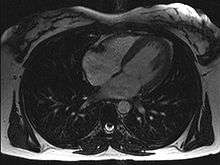

Magnetic resonance imaging (originally called nuclear magnetic resonance imaging), an imaging methodology based on aligning the spin axis of nuclei within molecules of the object being visualized using both powerful superconducting magnets and radio frequency signals and detectors. Cardiology uses are growing, especially since MRI differentiates soft tissues better than CT and allows for comprehensive exams including the quantitative assessment of size, morphology, function, and tissue characteristics in one single session. Current implementations for Cardiology uses are sometimes limited by lengthy protocols, claustrophobia and contraindications based on some complex metallic implants (pacemakers, defibrillators, insulin pumps), while artificial valves and coronary stents are generally not problematic. Image quality can be reduced by the continuous movement of heart structures. There is a promising future in cardiac MRI by more efficient scans, increasing availability of scanners and more widespread knowledge about its clinical application.